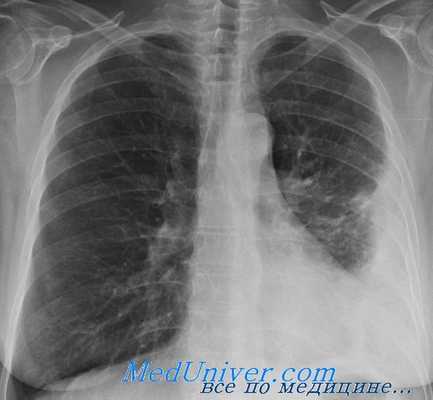

На рентгенограмме виден уровень - эмпиема плевры слева

Клинические проявления острой эмпиемы плевры характеризуются болью в боку, одышкой, подъемом температуры до 38— 39°С. Обычно, как и при других острых нагноительных процессах, вечерняя температура выше утренней на 2—3°С. В крови лейкоцитоз достигает 20-109—30-109/л (20 000 -30 000 в 1 мкл), отмечается сдвиг лейкоцитарной формулы влево. СОЭ увеличивается до 40—60 мм/ч. При физикальном исследовании больного обнаруживают ограничение подвижности соответствующей половины грудной клетки во время дыхания, притупление перкуторного звука в зоне расположении экссудата. Дыхательные шумы бывают резко ослабленными или вообще не прослушиваются. Рентгенологически на стороне эмпиемы определяется интенсивное затемнение, средостение смешается в противоположную здоровую сторорону. При пункции плевральной полости получают гнойную жидкость, в которой при бактериологическом исследовании обнаруживают неспецифическую или специфическую микробную флору.

В случаях прорыва в плевральную полость абсцесса легкого или туберкулезной каверны состояние больного может резко ухудшиться. Усиливается кашель, увеличивается количество мокроты. При этом откашливается содержимое плевральной полости, в которой над жидкостью скапливается воздух. Перкуторный звук приобретает коробочный оттенок, дыхание остается ослабленным. Рентгенологически верхняя граница экссудата бывает горизонтальной независимо от положения тела больного, над уровнем жидкости определяется воздушная полость — типичная картина пневмоторакса. В зависимости от степени коллапса легкого различают ограниченный, субтотальный и тотальный пиопневмоторакс.